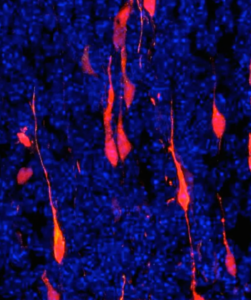

“O zika tem uma capacidade notável de infectar as células-tronco neurais, que são as ‘mães’ de todos os neurônios e formam o Sistema Nervoso Central”, ensina a biomédica.

Os experimentos do grupo de Garcez mostraram que sim: o contato com a substância neurotóxica dobrou a quantidade de células neurais mortas pelo zika em testes com organoides, ou “minicérebros” cultivados em laboratório.